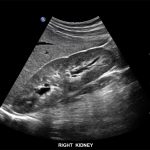

Imagini clinice:

Aplicatii: